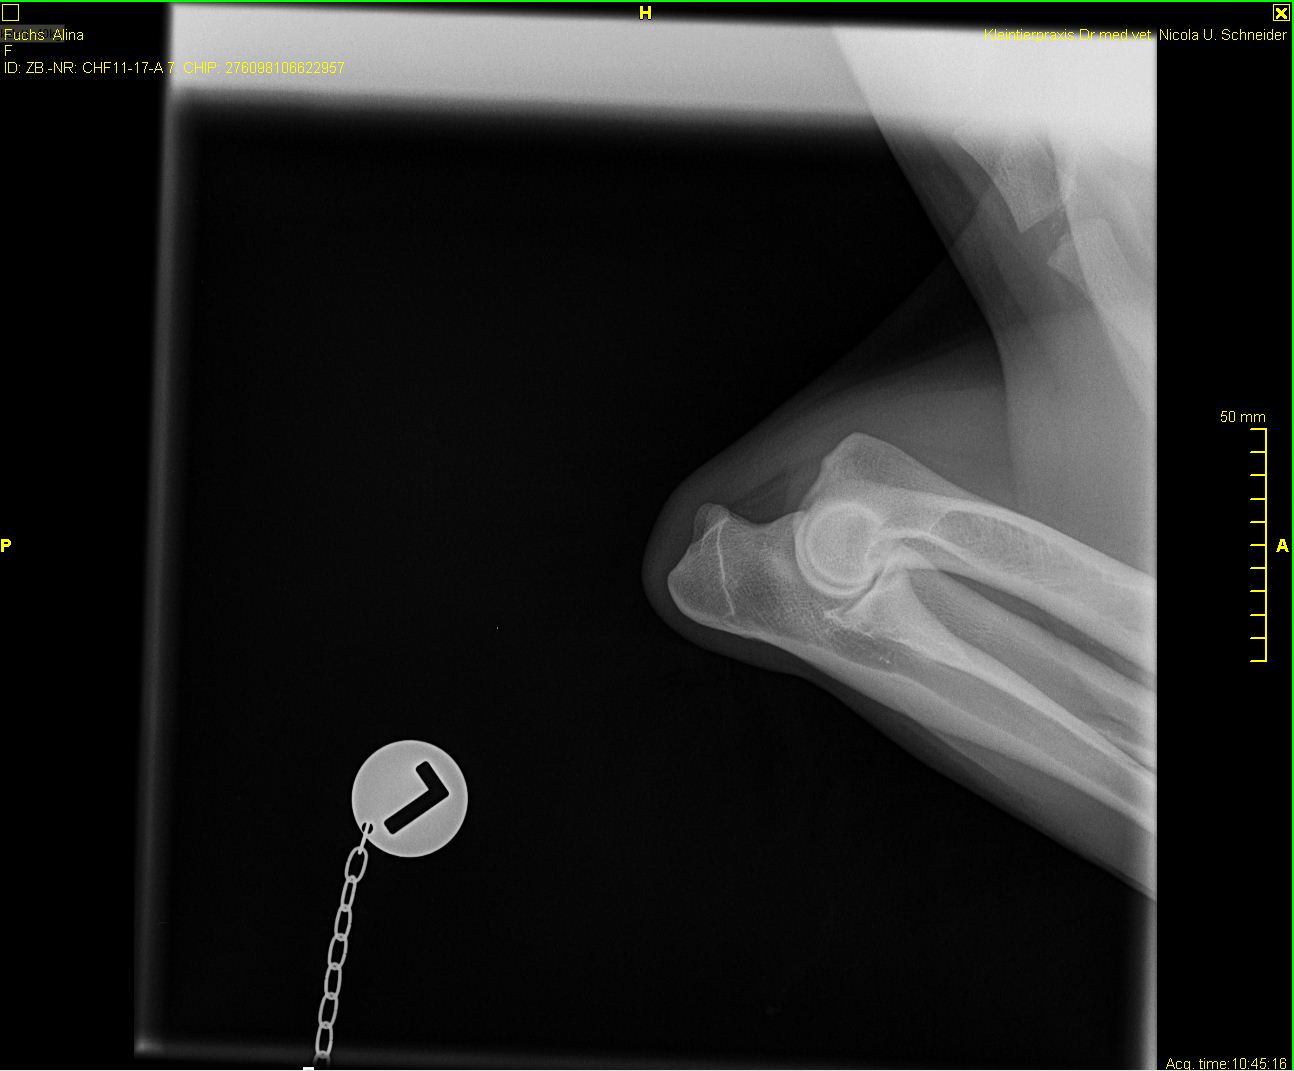

Alina - ED-Röntgen

-Alina-ed-links